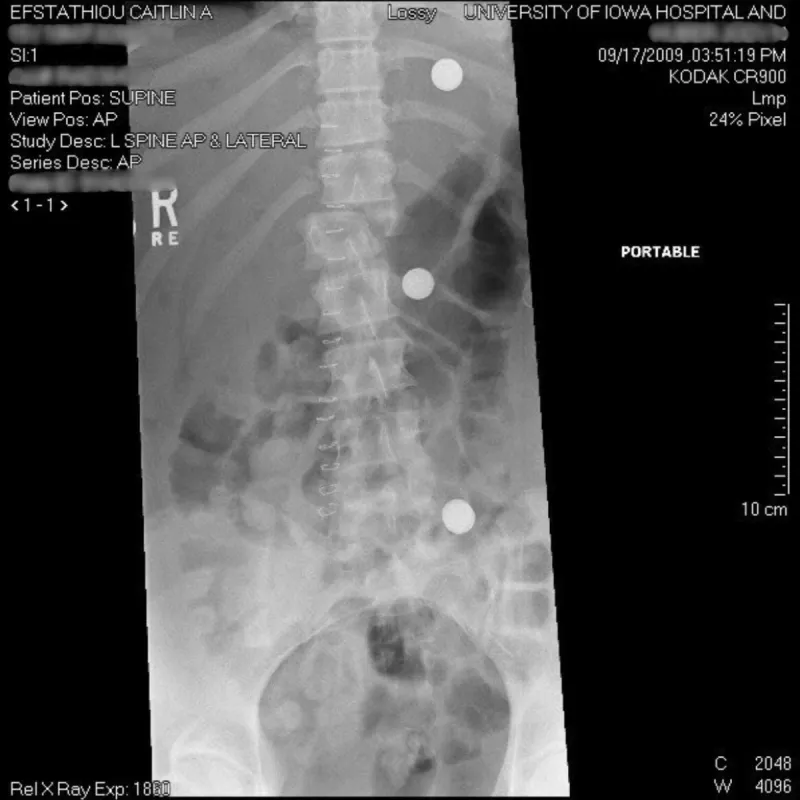

Efstathiou was transported to a Davenport hospital with internal bleeding, all her ribs broken, a lacerated liver, a broken leg, fractures in her hip socket, punctured lungs, a ruptured spleen, a broken back, and an arm with severe abrasions.

She spent four days undergoing surgeries and receiving care before her neurosurgeon determined the severity of the back injury required a referral to UI Health Care. She spent a month recovering in Iowa City.